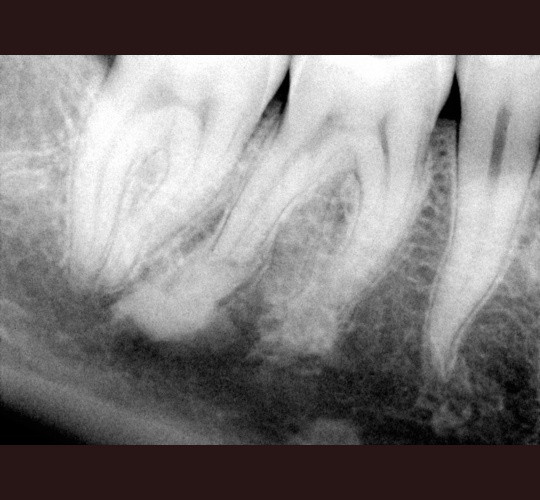

Read MoreEndodontic Treatment: Case #12- Four canalled lower first molar.

Unique parts are that there are 3 canals of the mesial root that join to one common apex (root end).